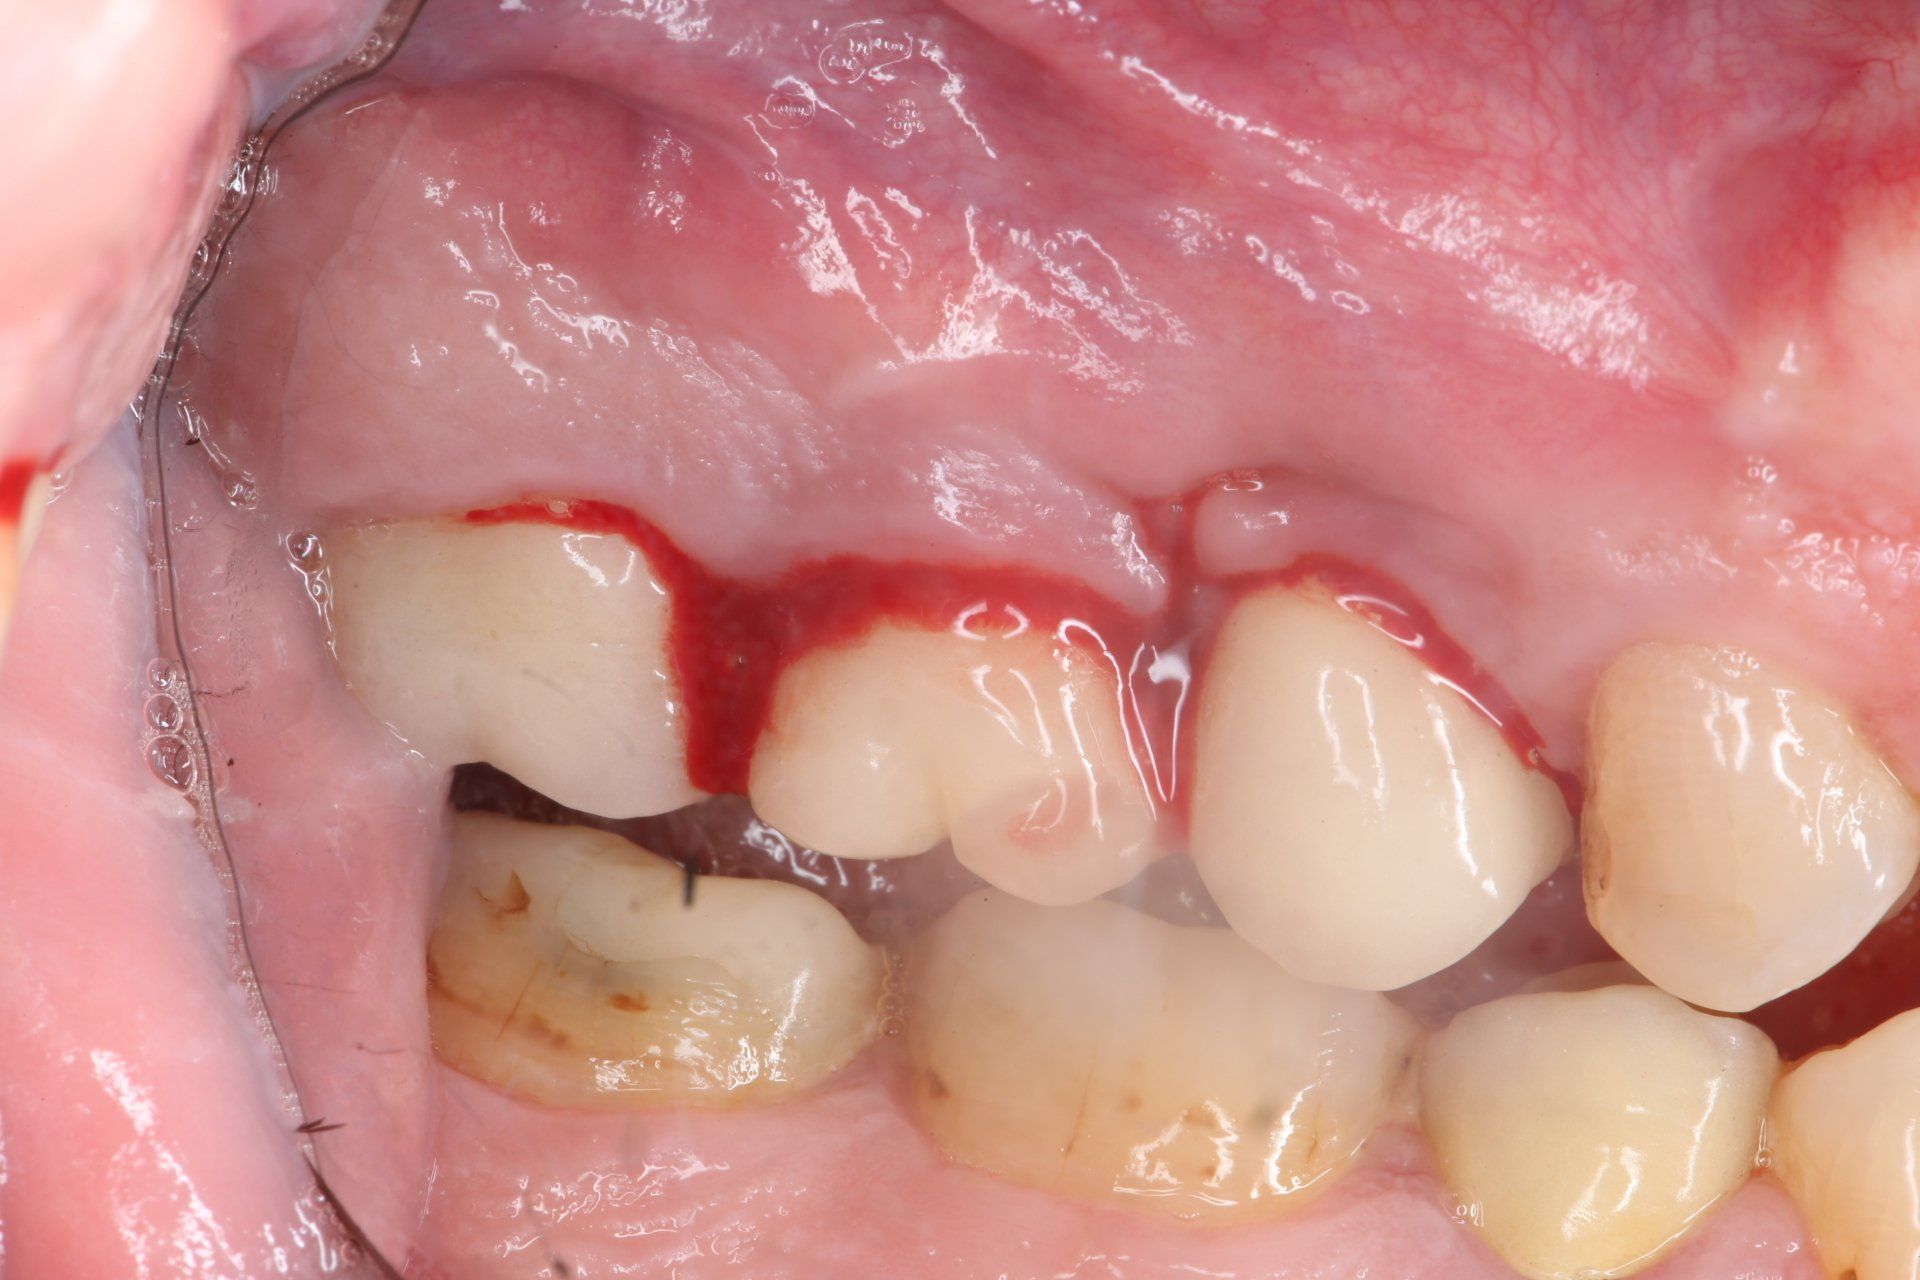

Il paziente si presenta al primo appuntamento (T0) lamentando dolore nella zona degli impianti. A seguito degli esami effettuati è stata diagnosticata una gengivite generalizzata e mucosite perimplantare (Fig. 2, 3, 4).

#dida Fig. 2: Foto frontale T0

#dida Fig. 3: Foto laterale di sinistra

#dida Fig. 4: Foto dettaglio palatale di sinistra

Come evidenziabile dalla cartella parodontale sottostante (Fig. 5) il P.I. corrisponde al 92%, il BoP al 99% con sanguinamento abbondante in zona 2.5 e 2.6 (Fig. 6). L’assenza di perdita di osso radiografica è stata confermata dalla radiografia endorale (Fig. 7).

#dida Fig. 6: Sanguinamento al sondaggio zona 2.5-2.6 a T0